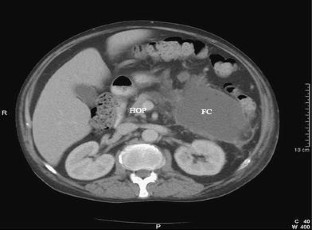

Unusual presentation of acute pancreatitis: an irreducible inguinoscrotal swelling mimicking a strangulated hernia

We report an unusual presentation of acute pancreatitis as a tender, irreducible, inguinoscrotal swelling mimicking a strangulated hernia. Lack of abdominal symptoms or signs can lead to misdiagnosis and unnecessary surgery.

Fig. 1.